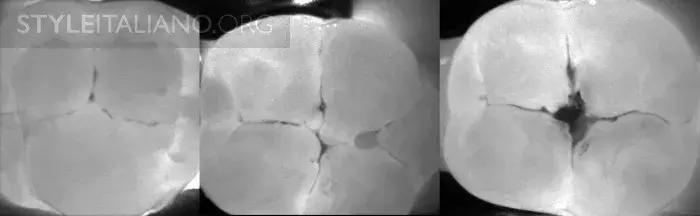

Рис. 30 — Трещина зуба на снимке.

Рис. 31 — Несколько трещин.

Рис. 32 — Вид поражения под трещиной.

Рис. 33 – Несколько трещин вблизи амальгамы.

Рис. 34 – Несколько трещин вблизи композитной реставрации.